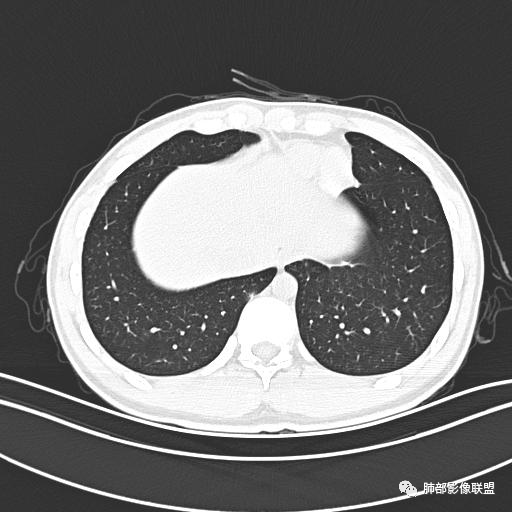

小强:青年,发热,皮疹;双肺散在结节,周围磨玻璃,点晕征,疱疹病毒感染,鉴别荚膜组织胞浆菌,结核。 大雄:青年,急性起病,发热伴全身皮疹2天,抗病毒治疗体温有下降。双肺随机分布大小不等类圆结节,“点晕征”。考虑水痘-疱疹病毒(VZV)血播询问接触史,查体皮疹分布以及形态基本可诊断。 王开金江津中心医院呼吸科:青年男性,起病急,病程短,以发热,皮疹为首发症状,感染指标以单核细胞升高为主,胸部ct双肺多发结界,周围有晕,点晕表现,随机分布,同意於老师意见,水痘疱疹病毒血流感染累及肺。 王秀仙:双肺多发大小不等结节,周围有晕,边缘模糊,呈点晕征表现。青年,急性起病,发热伴全身皮疹2天,抗病毒治疗体温有下降。考虑疱疹病毒。鉴别荚膜组织胞浆菌。 傅昌瑜:19岁男性,发热、全身皮疹2天,单核细胞增高,双肺多发结节,结节边缘见边界不清磨玻璃影。点晕征+发热、全身皮疹+单核细胞增高——考虑水痘-带状疱疹病毒肺炎。 一切∮随缘:年轻男性,发热,皮疹两天,实验室,CRP,PCT增高,影像:双肺多发散在磨玻璃结节,边界欠清,大小不等,呈点晕征改变,以血管束周围分布为主,局部血管束略增粗,其它无明显改变,考虑:1:病毒性肺炎(水痘疱疹病毒?不知道皮肤有无改变)2:真菌(组织胞浆菌,血管侵袭性肺曲霉)3:GPA4:寄生虫(实验室没有看到嗜酸细胞增高) 赵山河:双肺散在结节,周围有晕,边缘模糊,呈点晕征表现。青年,急性起病,发热伴全身皮疹2天,抗病毒治疗体温有下降。考虑水痘—疱疹病毒感染。洪桥爱:青年男性,发热、皮疹2天,伴瘙痒,皮疹于面部首发,之后进展至全身,虽然没有对皮疹进行描述,但是从出疹时间及皮疹进展情况,伴瘙痒,应该就是个水痘患者;CT提示双肺随机分布结节影,部分结节伴有边界不清晕征,考虑水痘血播肺。 刘强:年轻男性,急性起病,皮疹,发热,抗感染治疗体温下降,说明有效。影像表现为散在点晕征,感染类疾病谱(疱疹病毒,真菌,结核),结合年龄,皮肤皮疹,考虑水痘-疱疹病毒性肺炎。 小兜:男性,19岁,发热皮疹两天,颜面部至全身,CRP,降钙素及单核增高。CT示双肺散在小结节,周围伴磨玻璃影,点晕征,考虑为水痘-带状疱疹病毒(varicella-zoster virus,VZV)肺炎 必有路:青年,皮疹+发热+“点晕征”→水痘-疱疹病毒(VZV) 许慧良:青年男性患者,发热、皮疹2天,体温最高38.5℃,第3天皮疹扩展至全身,伴瘙痒,胸部CT:双肺多发随机分布的小结节,结节周边见边界模糊的晕征,考虑水痘病毒感染流心明智:男,19,急性起病,发热伴全身皮疹2天。出疹顺序头→全身,抗病毒有效。胸部CT:两肺多发大小不等类圆形实性小结节影,随机分布,结节周围环绕GGO,边界模糊,呈点晕征。出疹特点是关键,未提示。考虑:血播病毒性肺炎,水痘-疱疹病毒?麻疹?鉴别荚膜组织胞浆菌、TB、血管炎、寄生虫等。 浪迹天涯:病灶多为5-10mm大小结节,结节周围可见磨玻璃样的晕环,常多发,可分布于肺内任何区域,考虑水痘—带状疱疹病肺炎如果短时间内有新的一个区域浸润,更加能说明,